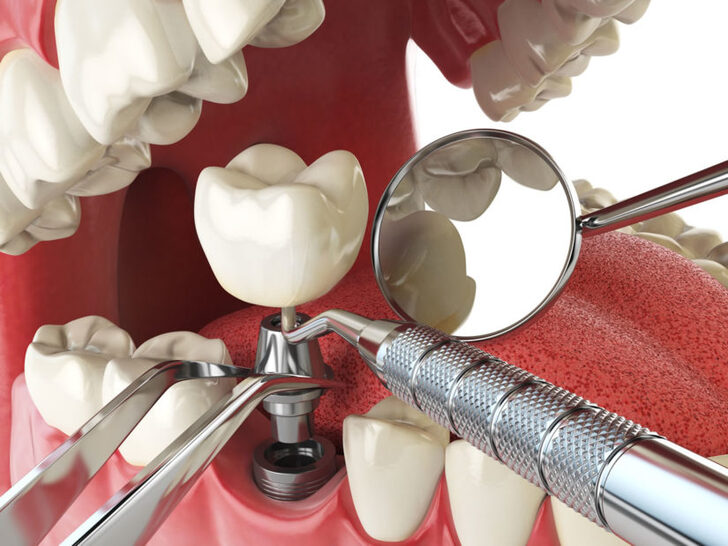

詢問過程中護理師拿著植體(人工牙根)模型為我們母女倆講解品牌差異性

這時候才知道原來要做植牙用的人工牙根-植體有分那麼多種類

各國廠牌看得眼花撩亂

植牙體系彷彿一個小型聯合國有來自台灣、德國、瑞士、韓國…很多種國家品牌

每個品牌各有優劣勢、植體價格同樣差距好幾萬元

經過幾番家庭會議討論後才決定植牙品牌、價錢